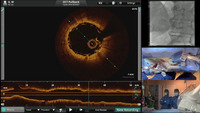

Zespół w składzie: dr Dariusz Ciećwierz, lek. Piotr Drewla, dr hab. Miłosz Jaguszewski, lek. Grzegorz Żuk, mgr Małgorzata Zielińska i mgr Roma Zapaśnik wykonał zabieg angioplastyki prawej tętnicy wieńcowej z implantacją bioabsorbowalnego pokrycia naczynia wieńcowego (BVS) w restenozie oraz bifurkacji z wykorzystaniem najnowocześniejszej techniki obrazowania wewnątrznaczynowego za pomocą optycznej tomografii koherencyjnej (ang. optical coherence tomography, OCT). Zabieg przeprowadzony 3 czerwca br. w Pracowni Kardioangiologii Inwazyjnej UCK transmitowano na żywo w ramach międzynarodowej konferencji kardiologii inwazyjnej „K-IMAGING Korea Cardiovascular Interventional Imaging Forum” w Seulu. Transmisja spotkała z bardzo pozytywnym odbiorem wśród uczestników warsztatów, jak i grona ekspertów z Azji, Europy i Ameryki Północnej, co zaowocowało propozycją współpracy w przyszłym roku. Transmisja była możliwa dzięki wsparciu TV Med wydawnictwa Via Medica.

W trakcie transmisji przeprowadzono ciekawą dyskusję na temat wskazań i techniki implantacji nowych wewnątrzwieńcowych pokryć bioresorbowalnych stosowanych coraz powszechniej w pracowniach inwazyjnych na całym świecie.

Obrazowanie metodą OCT stosuje się w Pracowni Kardiologii Inwazyjnej wybranych sytuacjach klinicznych od zeszłego roku. Pod koniec 2015 r. gdańska Pracownia przeprowadziła warsztaty obrazowania met. OCT dla pracowni hemodynamicznych województwa pomorskiego z udziałem prof. Juana Luisa Gutierrez-Chico z Niemiec, eksperta w dziedzinie obrazowania i kardiologii inwazyjnej.